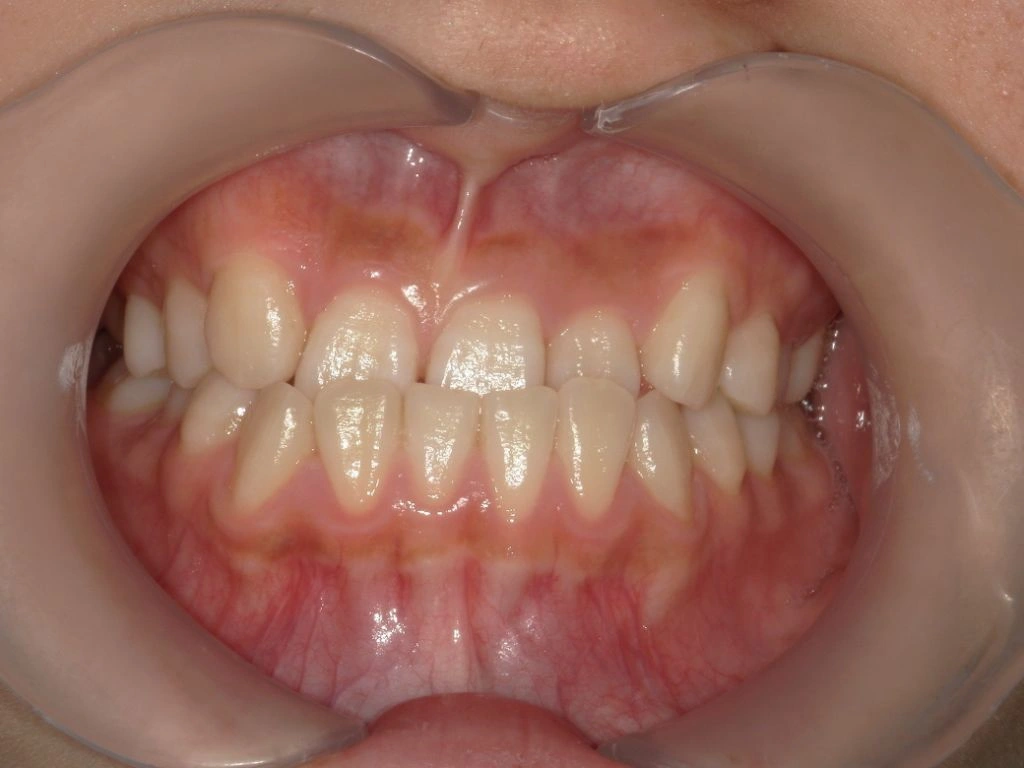

【治療後】

MSEを併用しながらワイヤー矯正が終了した状態です。本来の顎位で上下の正中(真ん中)が合ってきて概ね矯正治療としてのゴールが見えてきました。